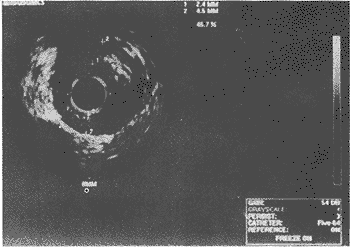

冠脉内超声检查左前降支近段、中段和回旋支21例,右冠状动脉近段6例。被检查的靶血管 共45段,均有不同程度的内膜增厚和斑块形成,其中41段偏心性斑块,4段向心性斑块根据 声学特征的不同显示软斑块11例,纤维斑块3例,其余均为钙化及混合性斑块(图1)。

图1 溶栓治疗后冠脉内超声显示血管仍存在严重狭窄